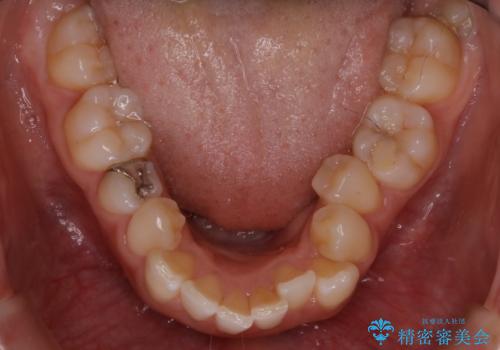

- 上顎の八重歯が気になるとのことで来院されました。

左側のかみ合わせは、歯1本分かみ合わせが前にずれていました。上顎左右の奥歯を2本抜歯しています。

下顎は、歯の側面を少し削ることで歯並びを整えました。